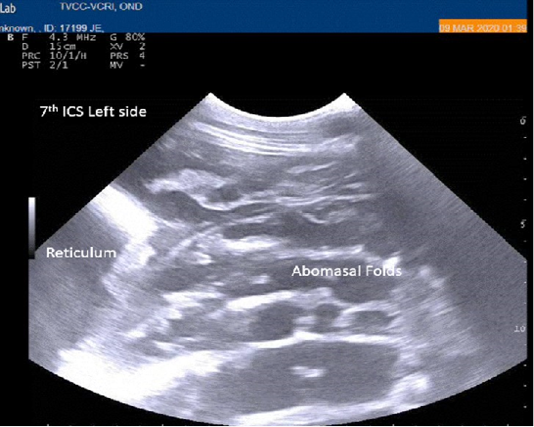

Figure 1

Percutaneous ultrasonography of left lateral thorax at 7th inter coastal space showed inflamed abomasal leaves with emptiness.